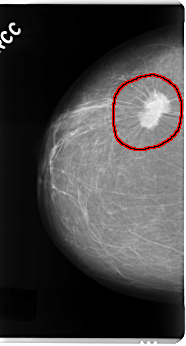

C_0121_1.RIGHT_CC

RIGHT_CC LINES 4832 PIXELS_PER_LINE 2592 BITS_PER_PIXEL 12 RESOLUTION 50 OVERLAY

FILE: C_0121_1.RIGHT_CC.OVERLAY

TOTAL_ABNORMALITIES 1

ABNORMALITY 1

LESION_TYPE MASS SHAPE IRREGULAR MARGINS SPICULATED

ASSESSMENT 5

SUBTLETY 5

PATHOLOGY MALIGNANT

TOTAL_OUTLINES 1

BOUNDARY